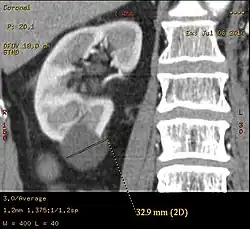

Category IIF

This category includes renal cysts with multiple thin septa, a septum thicker than hairline, slightly thick wall, or with calcification, which may be thick. It also includes intrarenal cysts larger than 3 centimetres (1.2 inches) if:

- there is no contrast enhancement (otherwise category III).[8]

- there is high attenuation or there is a maximum 25% of their walls visible outside the kidney (otherwise category II).[4]

Category IIF cysts have a 5–10% risk of being kidney cancer, and therefore follow-up is recommended. However, there is no consensus recommendation on the appropriate interval of follow up.[8]

Bosniak II cyst at the lower pole of right kidney with septations within.